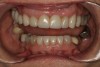

Fig 11. Semi-permanent self-cure composite provisionals Nos. 3 through 12 and 23 through 26 to establish function and esthetics and allow osseointegration of implant No. 9.

Figure 11

Fig 12. Removal of semi-permanent self-cure composite provisionals to restore teeth and osseointegrated implant No. 9.

Figure 12

Fig 13. Definitive restorations Nos. 3 through 12 (implant No. 9) and Nos. 23 through 26 seated.

Figure 13